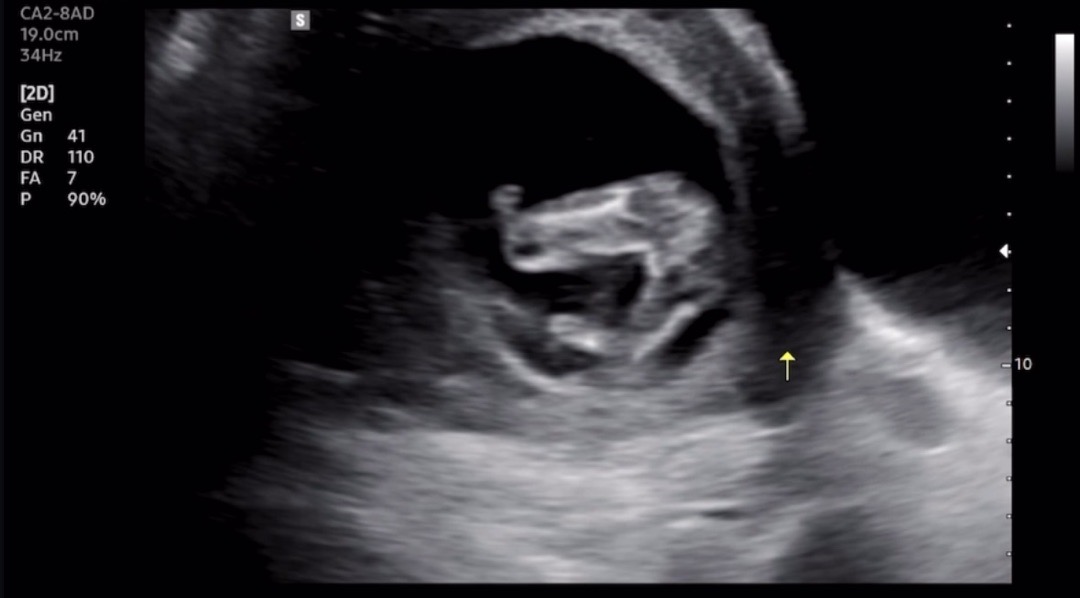

다리사이 초음파..! 어떤것 같나요?

14주차2일인데 어때보이나요?!투표해주세용..! 반전있을까요?